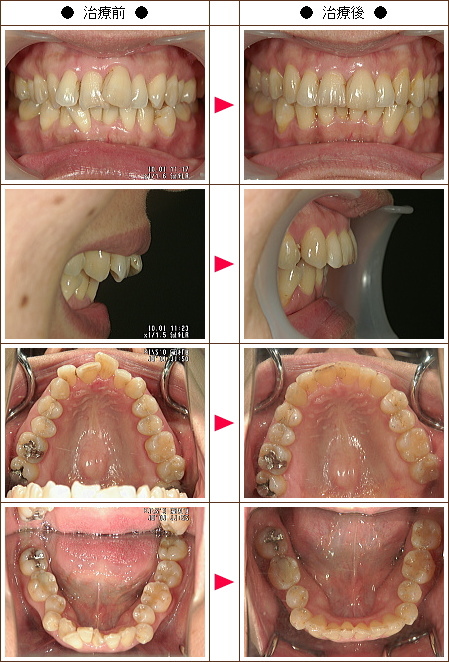

☆歯のデコボコ矯正症例[Y.O.様 40歳 女性]